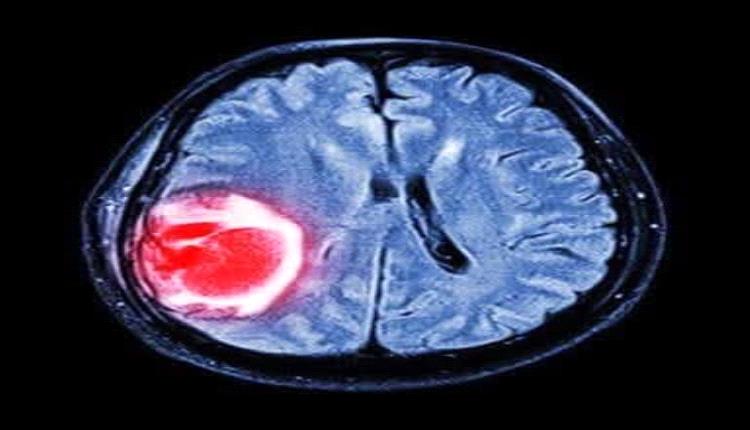

استشاري طب الاورام  والعلاج الكيماوي : مايو شهر التوعية بسرطان الدماغ

وسرطان الدماغ تشمل أورام المخ بكل أنواع الأورام التي تظهر داخل القحف أو في قناة العمود الفقري المركزية.

وهي تنجم عن انقسام غير طبيعي للخلايا ولا يمكن السيطرة عليه، غالبًا ما يكون ذلك في المخ نفسه، لكنه يحدث أيضاً في النسيج الليمفاوي، وفي الأوعية الدموية، وفي الأعصاب القحفية أو في أغلفة المخ (السحايا)، أوالجمجمة، أو الغدة النخامية، أو في الغدة الصنوبرية. داخل المخ نفسه، يمكن أن تكون الخلايا التي يحدث بها الانقسام عبارة عن خلايا عصبية[محل شك] أو خلايا دبقية، والتي تشتمل على الخلايا النجمية والخلايا الدبقية قليلة التغصن وخلايا البطانة العصبية). كما يمكن أن تتسبب السرطانات الموجودة في الأعضاء الأخرى (الأورام الخبيثة) في انتشار أورام في المخ.

هناك العديد من أنواع أورام الدماغ منها الحميدة ومنها الخبيثة (سرطانية). تؤدي أورام الدماغ إلى أعراض كألم الرأس، عدم وضوح الرؤية وأخرى وقد تؤدي لمضاعفات كفقدان الوعي، النوبات الدماغية وغيرها. من المهم تشخيص أورام الدماغ لأن بعض الأنواع يُمكن علاجها والشفاء منها أحياناً. تتوفر عدة إمكانيات علاج لأورام الدماغ وتشمل المعالجة الجراحية، العلاج بالأشعة والعلاج الكيماوي. وتتغير إمكانيات العلاج وفقاً لنوع الورم ومرحلته.